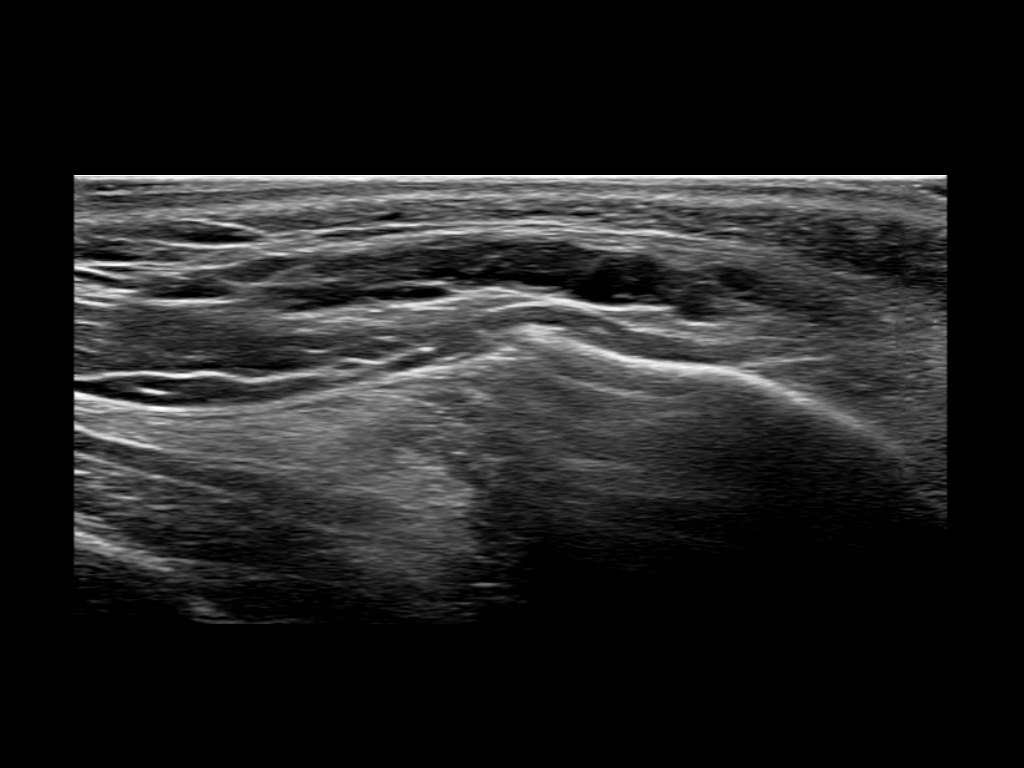

Study the first image to recognize the different layers. If you are sure about the layers, swipe to the second image to view the answer (if applicable).

Hover over an image to view the secondary image or click on the image title for more information.